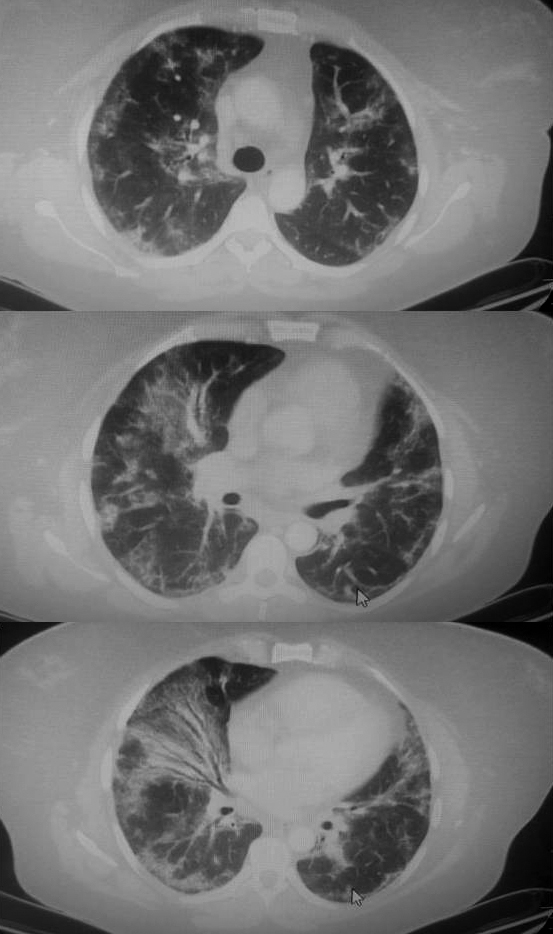

Resim 2. Üst loblarda yoğunlaşan ancak her iki akciğerde tüm loblarda tutuluş sergileyen konsolidasyon ve buzlu cam görüntüleri.

78 yaşında kadın hasta nefes darlığı yakınmasıyla başvurduğu dış merkezde akciğer oskültasyonunda iki taraflı raller duyulması ve pretibial ödem gözlenmesi nedeniyle kortikosteroid ve 2 ampül “lasix” yapılarak acil servisimize gönderilmişti. Parmak ucundan ölçülen satürasyon değeri 75 olan hasta hipertansiyon ve kronik obstrüktif akciğer hastalığı (KOAH) olduğunu ve evinde oksijen konsantratörü bulunduğunu ifade etmişti. Periferik kan incelemesinde; hematokrit %46 (RD: 31-42), nötrofil 7700/mm3, lenfosit 300/mm3, D-dimer 579 (RD: 0-243 ng/ml), LDH 410 (RD: 135-225 Ü/lt), üre 53 (RD: 16-48 mg/dl), sodyum 127 (RD: 135-145 mEq/lt), klor 85 (RD: 98-107 mEq/lt) idi. Toraks BT’de üst loblarda daha yoğun olmak üzere diğer lobları da tutan buzlu cam görüntüleri ve konsolidasyon alanları izlendi (Resim 2). Pulmoner arter çaplarının artmış olması, hastada kronik solunum yetmezliğine bağlı pulmoner hipertansiyon gelişmiş olabileceğini düşündürdü. e-Nabız sisteminden hastanın 8 ay önceki akciğer

Resim 3. Akciğer grafisinde kardiyotorasik indeksin arttığı üst zonlarda parahiler bölgeleri silen, tüm zonları tutan nonhomojen dansite artışları.

grafisine (Resim 3) ulaşıldığında opasitelerin daha önceden de var olduğu anlaşıldı. Yine e-Nabız sisteminden hastaya daha önce biyopsi yapıldığı ve sarkoidoz tanısı aldığı görüldü. Bu olgu, buzlu cam görüntüsü ile gelen her hastanın özgeçmişinin olabildiğince iyi sorgulanması ve e-Nabız sisteminin araştırılması gerektiğini; sarkoidoz hastalığında lenfopeni olabileceğini; belirgin hiler ve mediyastinal lenfadenopati olmadan dağınık buzlu cam opasiteleri ve konsolidasyon görülebileceğini gösterdi. Sarkoidoz tedavisi amacıyla kortikosteroid tedavi başlanması düşünülen hasta başka hastaneye sevk edildi.